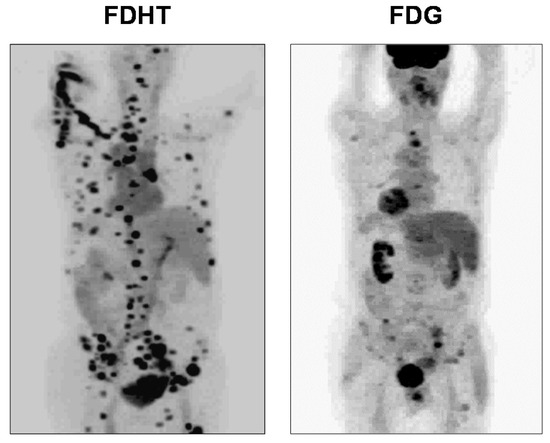

PET imaging of AR in men with advanced prostate cancer was published in 2004 and 2005 by me and my colleagues at Washington University Medical School in St. Louis [3] and by investigators at Memorial Sloan Kettering Cancer Center in New York (Figure 21) [115]. Clear FDHT uptake was evident in numerous lesions, with uptake being blocked following treatment with AR antagonists. Subsequent studies made comparisons between FDHT and FDG images in the same patient to characterize lesion heterogeneity, and comparative images in a series of patients showed both concordance (i.e., high or low uptake of both PET tracers) and discordance (FDHT high, FDG low, and the reverse) [185]. Some prognostic trends were correlated with these four distinct patterns of tracer uptake, with survival being greatest when FDG and FDHT images were concordant and lowest when FDHT uptake by lesions was very low. Survival was also inversely related to total lesion count and intrapatient heterogeneity; notably, PSA levels had little prognostic value [185]. Because often many more lesions are seen by PET imaging than can be biopsied, the imaging results can direct tissue sampling to the sites of possibly greatest concern (e.g., high metabolic activity (high FDG PET) and low AR responsiveness (low FDHT PET)) [185].

Figure 21.

FDHT-PET and FDG-PET image of prostate cancer in an individual with FDHT-avid disease. (Images provided by Dr. Steven Larson, Memorial Sloan Kettering Cancer Center.)

The predictive and prognostic role of AR in prostate cancer is rather different than that of ER in breast cancer. With ER-positive breast cancers, endocrine therapies often become less effective in advanced disease; so PET imaging of ER with FES and ER functional status by serial FDG- or FFNP-PET with an estradiol challenge can provide additional predictive value for benefit from continued endocrine therapies. By contrast, as long as AR is present in prostate cancer, it typically remains an effective target for hormone-directed therapies, even in advanced stages of castration-resistant prostate cancer (CRPC), although increasingly powerful endocrine strategies are needed [186]. The conversion from CRPC to neuroendocrine-type cancer typically involves loss of both AR and responsiveness to AR-targeted therapies [187]; so, FDHT-PET might prove useful in identifying this clinically significant progression by imaging.